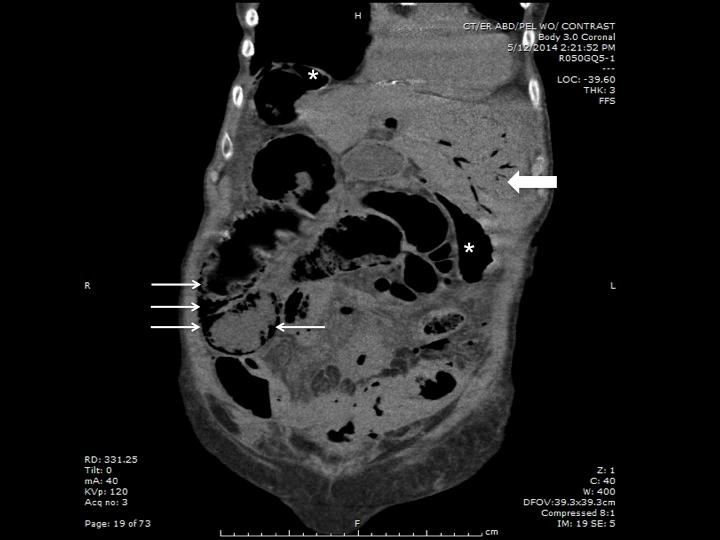

Hepatic portal venous gas: findings on ultrasound and CT.

West J Emerg Med. 2014 Nov;15(7):893-4. doi: 10.5811/westjem.2014.9.23276. Epub 2014 Oct 28.